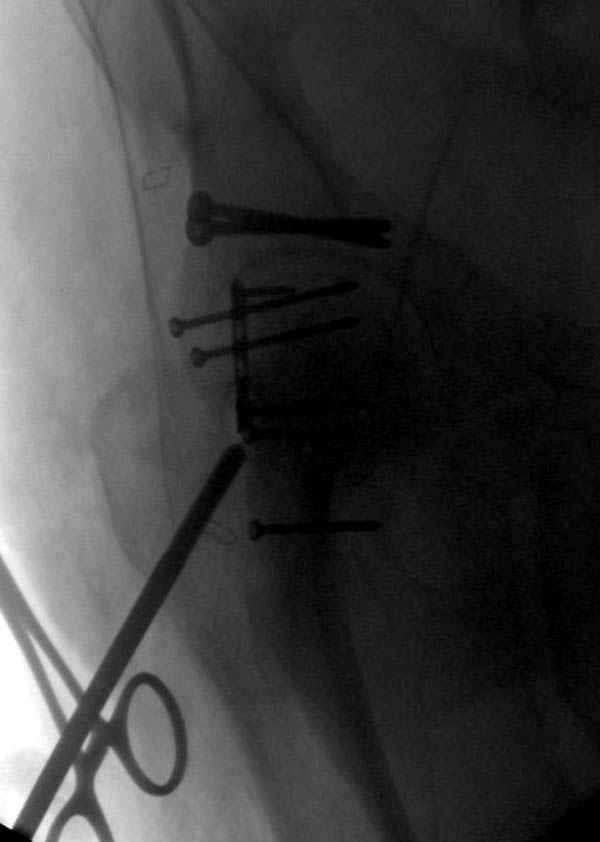

Имя     : 4 Proximal hum+acetabulum CRM.jpg

Url     : http://weborto.net:8080/pipermail/ortho/attachments/20071130/be03ce6b/attachment-0006.jpg